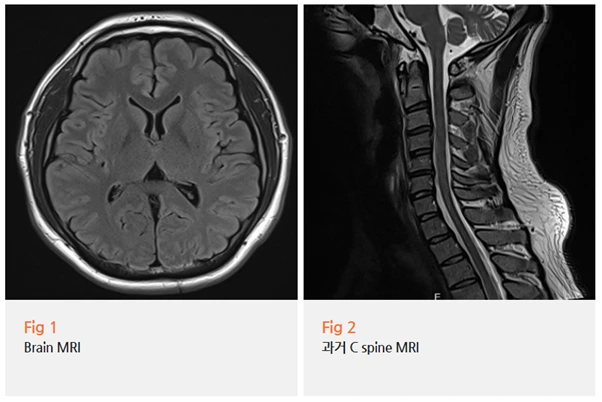

그래서 저는 환자분께 뇌 MRI를 권유드렸습니다.

검사 결과가 나왔을 때 일단 한숨을 돌렸어요.

다행히 뇌 영상검사에서는 특이 소견이 없었습니다.

하지만 여기서 끝이 아니었습니다.

뇌는 정상이었지만, 증상은 분명히 있었어요.

오른쪽 뒤통수 통증 찌릿한 느낌과

눈 떨림이 계속되고 있었으니까요.

그래서 저는 목 MRI를 자세히 살펴봤습니다.

그리고 원인을 발견했어요.

상부 경추, 그러니까 목 위쪽 부분에

기능장애가 확인된 거예요.

뇌는 정상이세요. 그런데 목에 문제가 있어요.

목 디스크와 경추 기능장애 때문에

뒤통수 통증과 눈 떨림이 나타난 거예요.